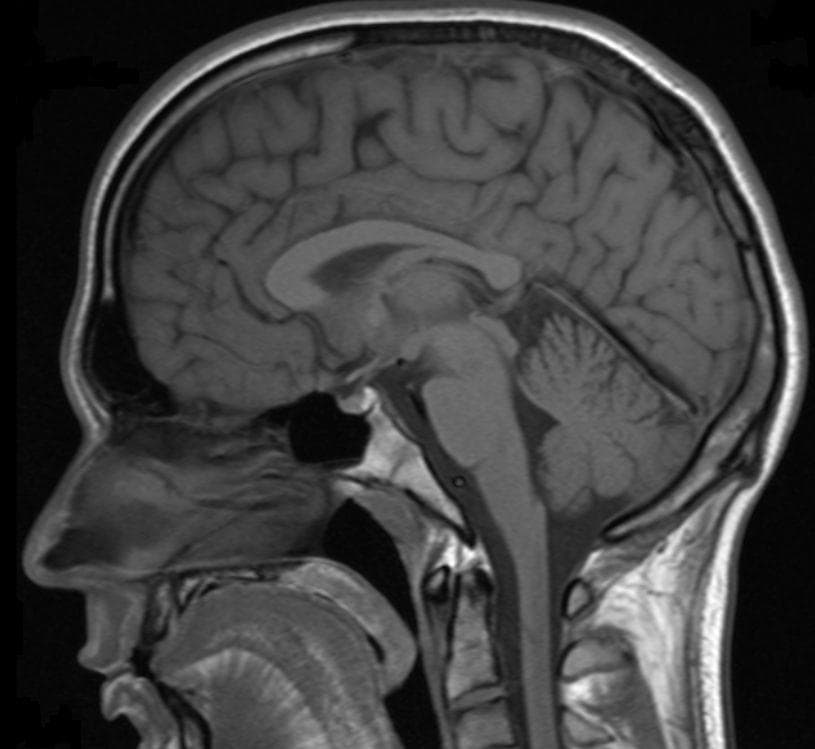

Researchers in New York recently moved closer to answering the question of what happens after we die - at least, in the immediate sense. The team of researchers found that while the heart stops, the brain continues to function slightly. Specifically, the part of the brain that keeps functioning post-mortem is the part which is responsible for consciousness.

Consciousness, in the simplest definition, is awareness. However, the neuroscience behind awareness is not well understood - at least not as well understood as neuroscientists would like. The human brain has billions of interacting neurons that process information.

The heart pumps blood to the rest of the body, including the brain, so that it can function. When our human brain absorbs and computes information that we take in, some scientists believe this is the phenomenon of consciousness.

Medically, expiration occurs when the heart stops circulating blood. When the heart stops pumping blood to the rest of the body, the brain ceases to function. The lack of blood circulation causes the body's temperature to drop and also causes breathing to cease. Without the blood flow of oxygen to the brain, the organ begins the process of dying along with the rest of the body.

If the brain is the control center for life, the heart is the core component that feeds the brain to keep it operating. When the heart stops pumping blood and breathing stops, clinical death has occurred.